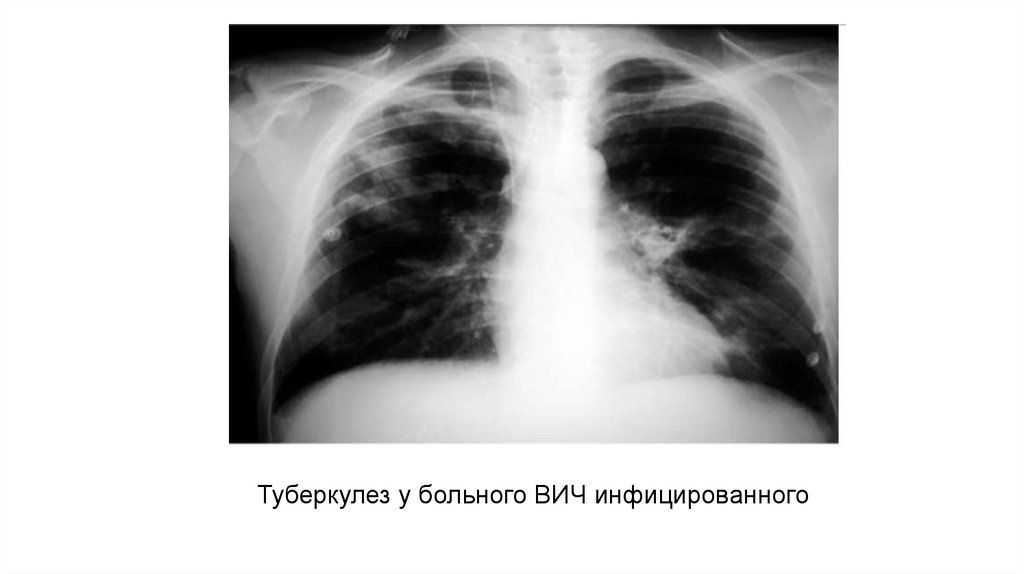

Туберкулез у больного ВИЧ инфицированного